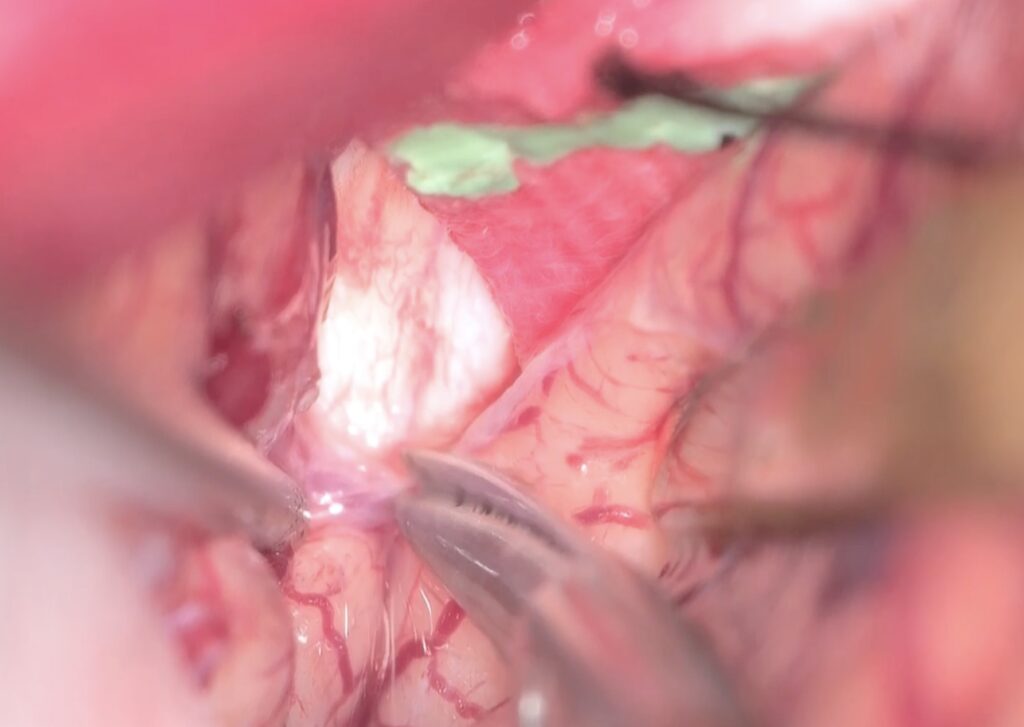

半球間裂の癒着が少なく、atraumaticに綺麗に開けることができました。

両側のGyrus rectusを剥離、前頭底にいたり、視神経と下垂体茎が見えます。

Trans-lamina terminalis approach、何度もやった古典的なアプローチです。A2と伴奏し縦走する視床下部動脈を温存して、その間隙から腫瘍を減圧していきます。